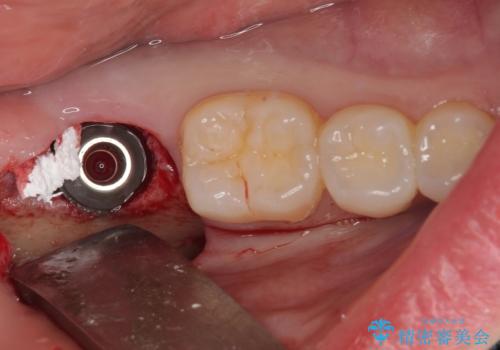

インプラント埋入と同時に仮歯を装着するために、事前に仮歯を用意し、速やかにインプラント埋入を行うこととしました。

抜歯された骨の穴は、インプラント埋入時にはまだ大きな窩洞となっていましたが、径の大きいワイドインプラントを選択することで、埋入時に十分な安定を獲得することができました。

後方には欠損が残っていたため、補填材を填入しました。

術後にインプラントが骨から脱落することがありますが、特筆するトラブルなどなく、最短の3ヶ月で治療を終えることができました。